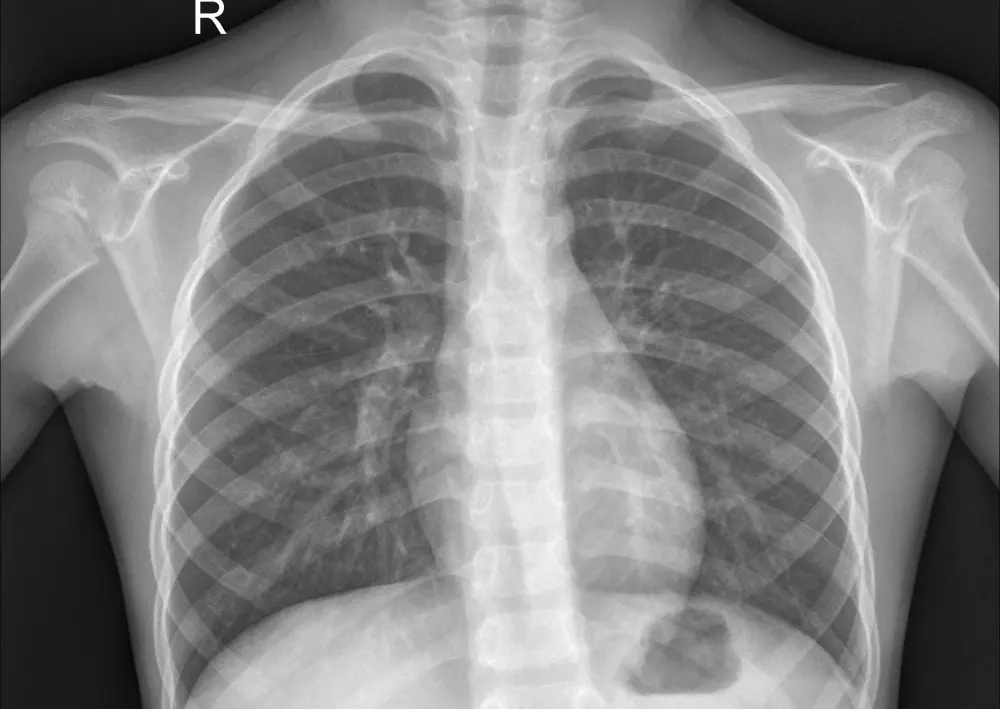

نموذج ذكاء اصطناعي باستخدام تقنيات Deep Learning لتحليل صور الأشعة الصدرية (Chest X-Ray) واكتشاف الإصابة بالالتهاب الرئوي (Pneumonia). المشروع يعتمد على شبكة CNN مدربة لتحليل الصور الطبية بدقة، مع توفير واجهة ويب بسيطة باستخدام Flask لرفع صورة الأشعة والحصول على النتيجة مباشرة. ما ستحصل عليه: * كود المشروع كامل بلغة Python * نموذج الذكاء الاصطناعي المدرب * تطبيق Flask لتحليل الصور * شرح طريقة تشغيل المشروع